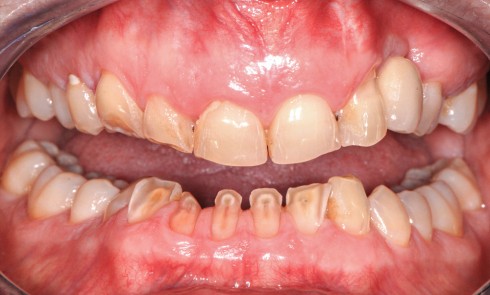

Article réservé à nos abonnés Réhabilitation occlusale temporaire selon les critères occlusaux fonctionnels

Une réhabilitation occlusale fonctionnelle est indiquée en cas de défaillances des guidages d’entrée et de sortie de cycles de mastication...